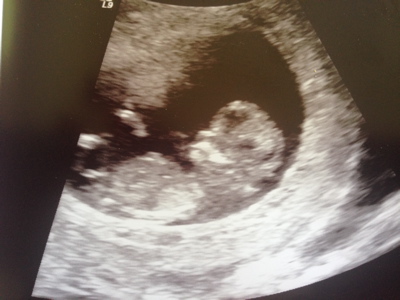

Hello! I'm new to this forum but I'd love to hear what you guess from our 12 week 0 day ultrasound. I really appreciate you taking the time to guess. Skull and Nub guesses would be great! Thanks so much!